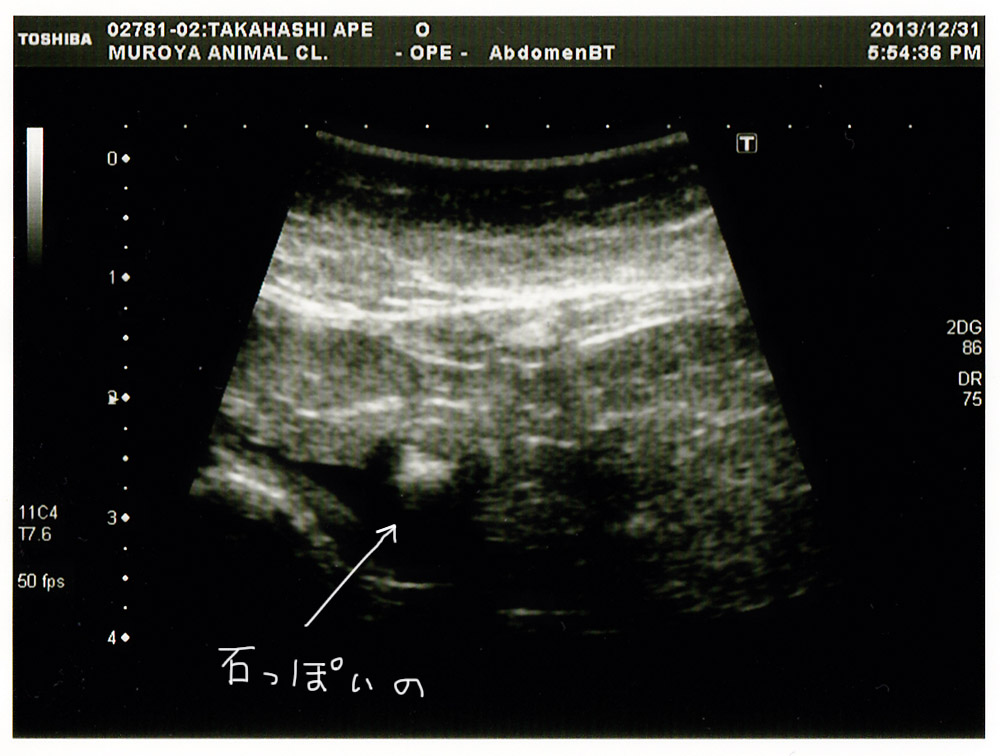

前回の膀胱の様子。

石っぽいものがあったけれど、今日エコー撮ったら

バラバラに溶けていました。

結石は前回だと割りとハッキリ移ってましたが、バラバラに溶けたようです。

エコーは病院で見てみる方がまだわかりやすいです(;´∀`)